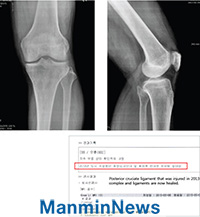

±âµµ Àü: ³»Ãø °üÀý ¸éÀÌ ¿ÜÃøº¸´Ù »ó´ëÀûÀ¸·Î Á¼À½. ±âµµ ÈÄ: ÈĹæ½ÊÀÚÀδë ÈÄ¿ÜÃø Àδ밡 Ä¡À¯µÊ.